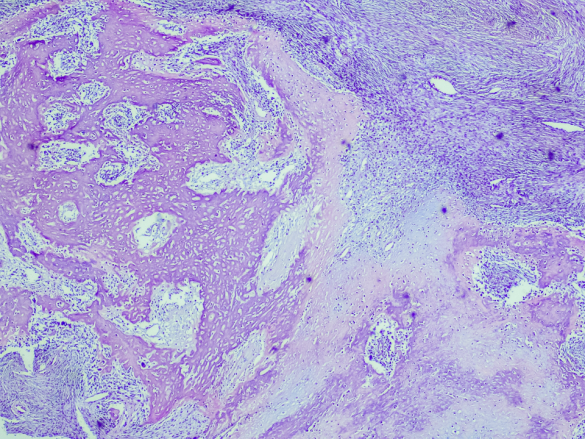

O osteossarcoma (OS) é uma neoplasia óssea primária, caracterizada pela proliferação descontrolada de células mesenquimais malignas com capacidade de produção de tecido osteóide. Essa condição representa um desafio significativo na área da saúde, afetando principalmente crianças, adolescentes e adultos jovens, com maior incidência na segunda década de vida e predominância no sexo masculino (Burger et al., 2018).

O diagnóstico precoce do OS é crucial para o sucesso do tratamento e para a melhoria do prognóstico do paciente. A apresentação clínica inclui dor óssea progressiva, aumento de volume do membro afetado e limitação de movimento, podendo ocorrer fratura patológica em alguns casos (Burger et al., 2018). A investigação diagnóstica envolve exames de imagem, como radiografia, cintilografia óssea, tomografia computadorizada e ressonância magnética, além de biópsia para confirmação histológica (Brasil, 2004).